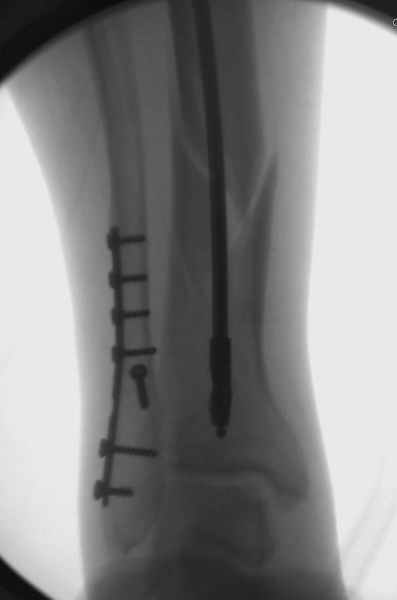

У меня молодой врач на линии, снимки отправил через эл. почту,

спрашивает что делать с больным который поступил недавно, фермер 55 лет падение при пьяной драке в баре, года два назад перенес операцию на лодыжке, на снимках и КТ перелом без вовлечения сустава,

Здесь мы использовали новый Synthes Nail с дополнительными дырками, в проксимальной части 4: по две косых и поперечные (один стандартный а другой динамический), в дистальной части две поперечные, прямая и косая. Вес больного более 120 кг, нагрузку начнем через месяц.

Получилось красиво, поздравляю. Вверху можно было ограничиться одним винтом во фронтальное статическое отверстие, зачем два 45-градусных?

При такий спирали задний край tibia может быть сломан - нет ли этого в данном случае? На всякий случай можно было ввести 1-2 винта 4,5 мм спереди назад мимо гвоздя. Хотя самый дистальный блокирующий винт, возможно, зацепил этот отломок. А какой тут диаметр гвоздя и locking винтов?